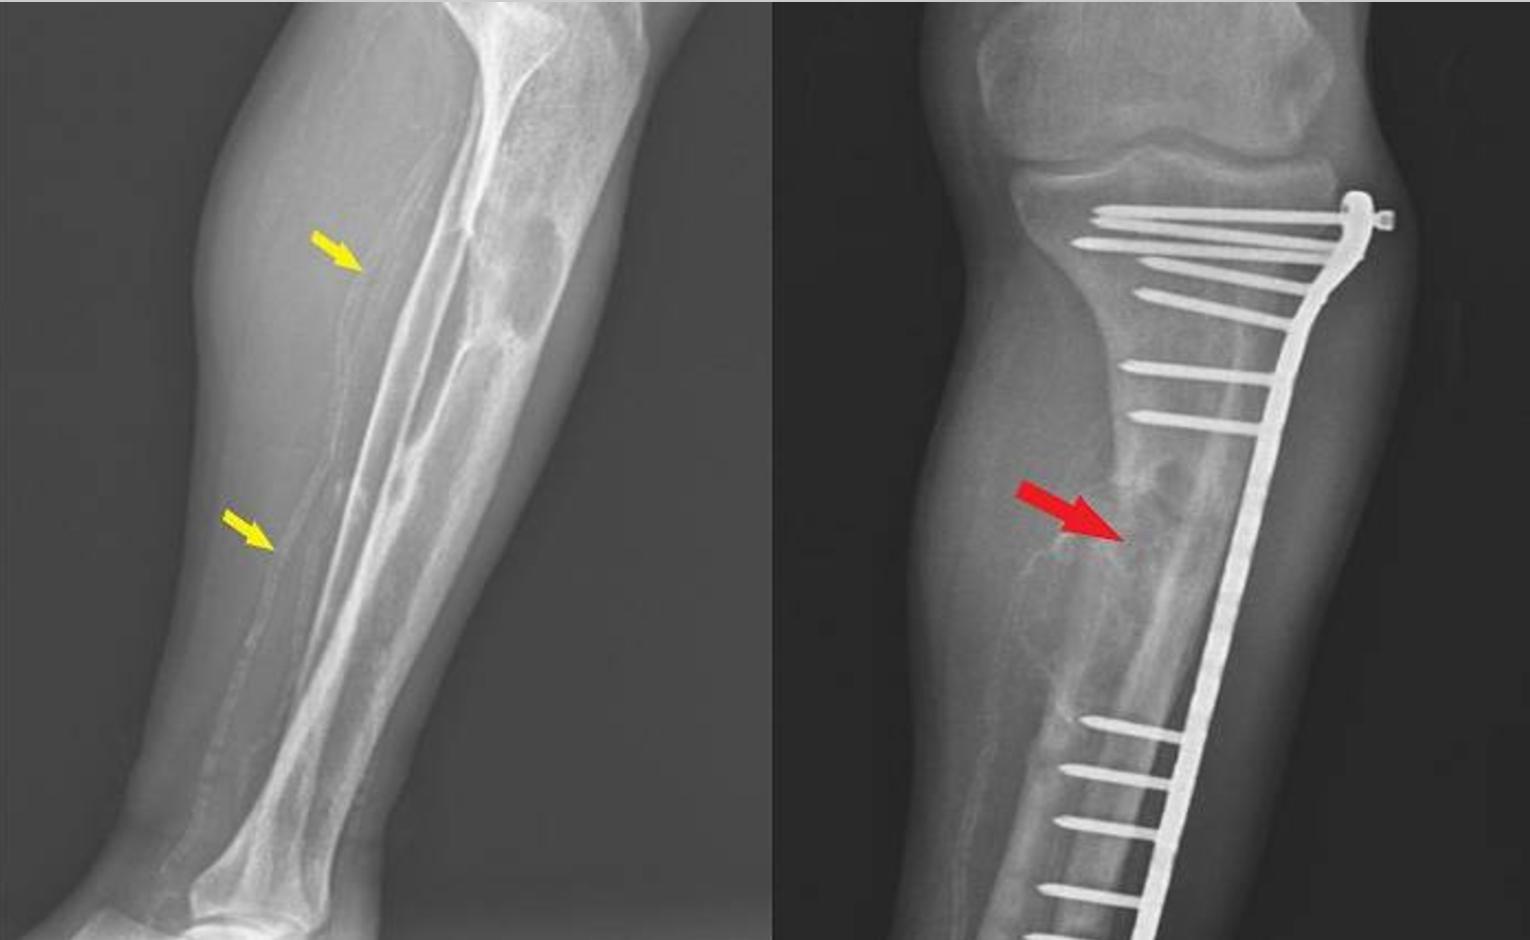

实验室结果如下:葡萄糖:92 mg/dL,血尿素氮:56 mg/dL、肌酸酐:7.8 mg/dL;钠:137 mEq/L,钾:4.5 mEq/L;钙:9.7 mg/dL,血清25-OH维生素D:12 ng/mL,白细胞:9200/µL,血红蛋白:8.2 g/dL,血小板:390 × 10³/µL。患者接受了回肠手术、甲状旁腺切除术(具体不详)和腿部骨折手术病史(图3)。此外,患者多年来一直有肌肉无力和骨痛的症状。

图3 腿部的X射线照相术。黄色箭头显示胫骨动脉中的血管钙化,红色箭头显示胫骨上OFC